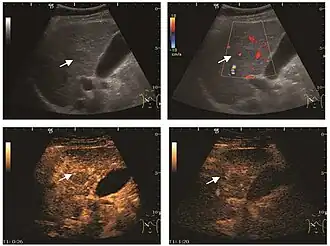

HCC appearance on 2D ultrasound is that of a solid tumor, with imprecise delineation, with heterogeneous structure, uni- or multilocular (encephaloid form). An "infiltrative" type is also described which is difficult to discriminate from liver nodular reconstruction in cirrhosis. Typically HCC invades liver vessels, primarily the portal veins but also the hepatic veins . Doppler examination detects a high speed arterial flow and low impedance index (correlated with described changes in tumor angiogenesis). The spatial distribution of the vessels is irregular, disordered. CEUS examination shows hyperenhancement of the lesion during the arterial phase. During the portal venous phase there is a specific "wash out" of ultrasound contrast agent (UCA) and the tumor appears hypoechoic during the late phase. Poorly differentiated tumors may have a stronger wash out leading to an isoechoic appearance to the liver parenchyma during portal venous phase. This appearance was found in approx. 30% of cases. The described changes have diagnostic value in liver nodules larger than 2 cm.

Ultrasound is useful in HCC detection, stadialization and assessing therapeutic efficacy. In terms of staging related to therapy effectiveness, the Barcelona classification is used which identifies five HCC stages. Curative therapy is indicated in early stages, which include very early stage (single nodule <2 cm), curable by surgical resection (survival 50-70% five years after surgical resection) and early stage (single nodule of 2–5 cm, or up to 3 nodules <3 cm) which can be treated by radiofrequency ablation (RFA) and liver transplantation. Intermediate stage (polinodular, without portal invasion) and advanced stage (N1, M1, with portal invasion) undergo palliative therapies (TACE and sorafenib systemic therapy) and in the end stage only symptomatic therapy applies.